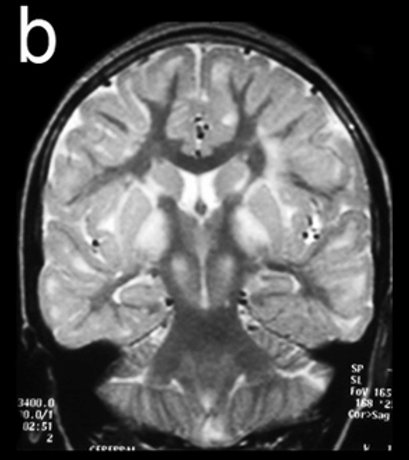

COR T2 FSE

The coronal T2 FSE imaging in studies investigating brain structure, connectivity, and pathology. These images provide valuable data for understanding normal brain development and function, as well as the mechanisms underlying neurological disorders.